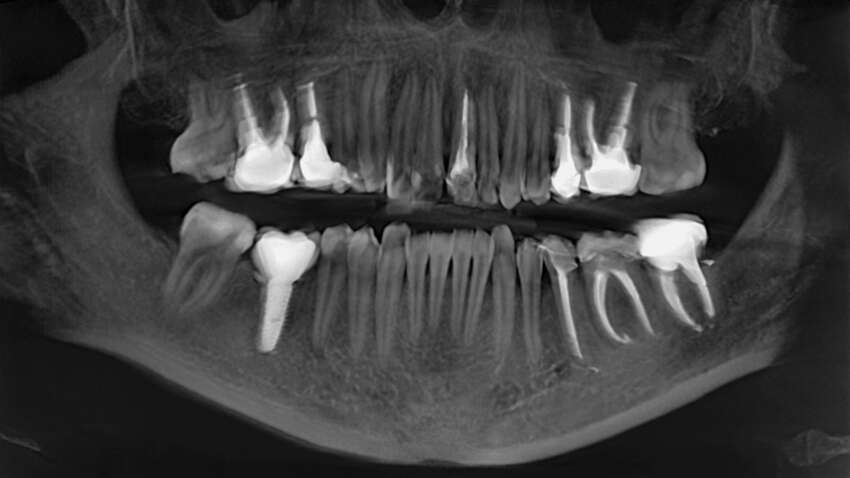

Ученые заявили, что люди в скором будущем смогут выращивать новые зубы вместо имплантов. Такая технология уже проходит экспериментальные испытания и может изменить навсегда стоматологию. Если раньше единственным вариантом потери зуба была установка металлических имплантов или съемных протезов, то теперь речь идет о возможности восстановления собственных тканей пациента – естественным путем.

Об этом сообщает "Popular Mechanics". Исследователи создали гидрогель, имитирующий среду роста зуба, где клетки взаимодействуют между собой и начинают формировать структуры, похожие на естественные. По словам авторов проекта, это открывает путь к созданию зачатков зубов, которые с течением времени могут дорастать непосредственно в челюсти человека. Ученые уже вырастили экспериментальные образцы с корнями и эмалью, используя клетки десен человека и клетки мышей.

Подобные исследования продолжаются и в Японии. Там компания Toregem Biopharma уже готовит первые клинические испытания препарата, активирующего "спящий" ген роста зубов. Если результаты будут успешными, к 2030 году появится лекарство, способное стимулировать рост нового зуба после потери постоянного.

Фактически это означает, что медицина переходит от протезирования к биологическому восстановлению. Вместо искусственных имплантов, которые с течением времени изнашиваются или отторгаются организмом, человек сможет "вырастить" собственный зуб – с нервами, эмалью и корнем.

Если технология оправдает ожидания, через несколько лет стоматологи не будут ставить импланты – они будут просто помогать вашим зубам вырасти снова.